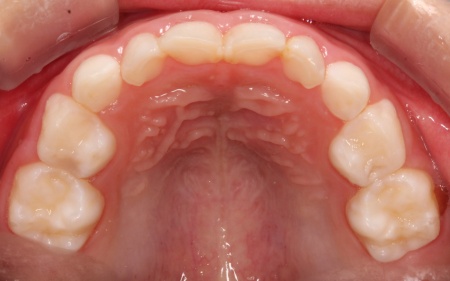

治療前

診断結果 拝見したところ、乳歯が隙間なく密集して生えている状態でした。

通常、乳歯の時期には歯と歯の間に発育空隙(はついくくうげき)と呼ばれる自然な隙間や、犬歯の前後に霊長空隙(れいちょうくうげき)と呼ばれる特徴的な隙間があります。

この隙間は、将来永久歯が生えるために必要なスペースを確保するためのものです。

しかし、患者様はこれらの重要な隙間がほとんど見られませんでした。

今のままでは、今後永久歯が適切な位置に並ぶためのスペースが不足すると考えられます。